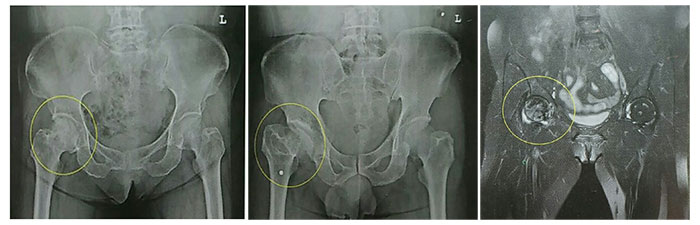

무혈관성 괴사란 혈액 순환 장애로 인해 혈액 공급이 원활하지 못하여 뼈가 썩는 병입니다. 대퇴골두 무혈관성 괴사는 허벅지 뼈, 즉 대퇴골의 머리 부분에 피가 통하지 않아 이 부분이 괴사 하게 되는 것입니다. 대부분 30~50대에게 발생하고, 여성보다는 남성에게 더 많이 발생합니다. 약 60% 이상은 양쪽 고관절의 대퇴골두 무혈관성 괴사를 겪습니다. 대퇴골두 무혈관성 괴사를 일으키는 위험 인자로는 음주, 부신피질 호르몬 투여, 고관절 부위 외상, 잠수병, 통풍, 혈청지질 이상, 만성 신질환, 만성 췌장염 등이 있습니다. 이 중에서도 음주와 부신피질 호르몬제가 전체 원인의 90% 정도를 차지합니다.